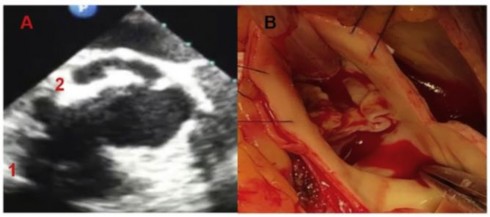

Hình 2. A: Hình ảnh trên siêu âm tim qua thành ngực (1-ổ aps xe vòng van ĐMC; 2- Hỉnh ảnh van ĐMC hai cánh van). B: Hình ảnh van ĐMC hai cánh van kiểu trước-sau nhìn trực tiếp trong mổ.

Trường hợp lâm sàng, bệnh nhân nam 56 tuổi (BN 71), được chẩn đoán hẹp hở van ĐMC, áp xe vòng van ĐMC/Van ĐMC bất thường hai cánh van.

Bệnh nhân được phẫu thuật tái tạo lại van ĐMC hai cánh, vá ổ áp xe vòng van bằng miếng vá màng ngoài tim.